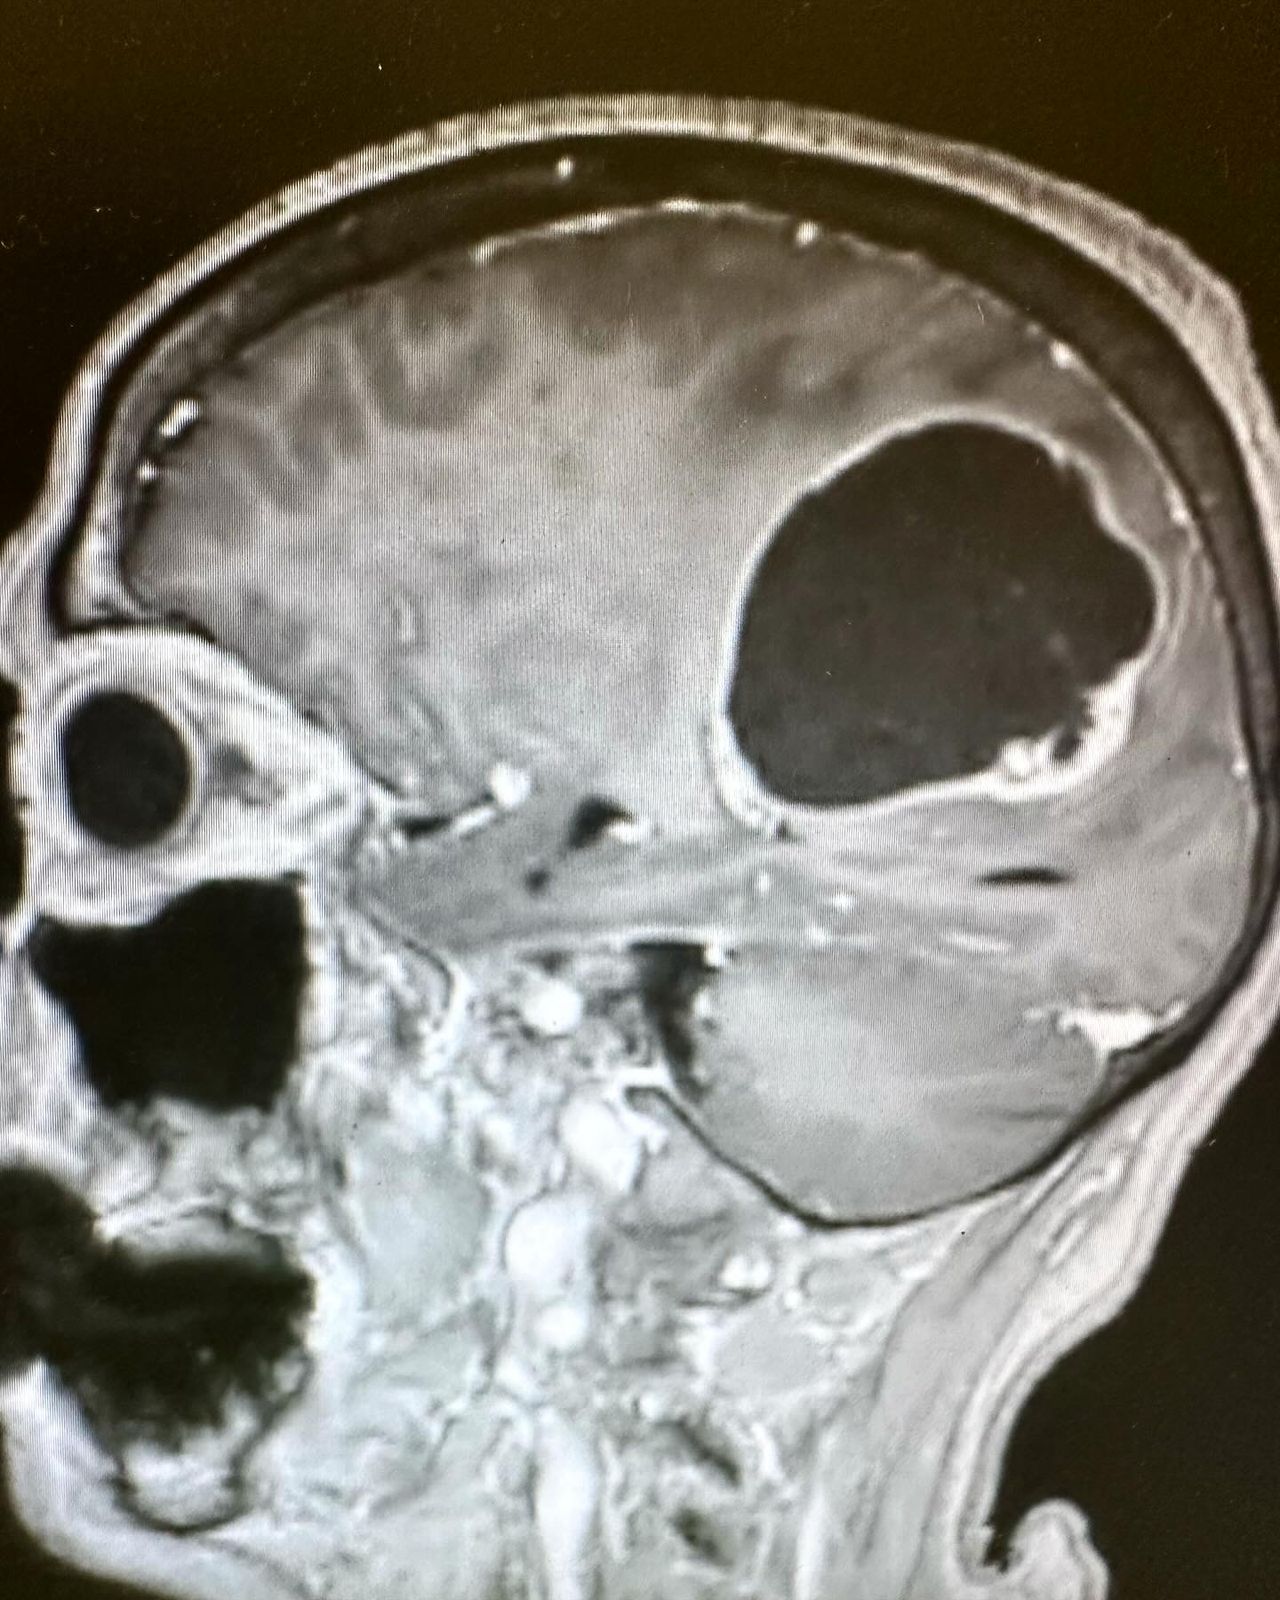

- Microchirurgia cerebrale: tumori (Meningiomi, gliomi, neurinomi ecc.) e malformazioni vascolari (Aneurismi, MAV, angiomi cavernosi, FAVD)

- Neuronavigazione, con incisioni minime e minicraniotomie (tailored-craniotomy)

Nel corso della mia formazione ho lavorato presso vari ospedali, tra cui l’Ospedale Borgo Trento di Verona, gli Ospedali Sant’Andrea e San Filippo Neri di Roma, l’Hospital La Paz di Madrid, approfondendo le mie conoscenze sulle patologie vertebrali e cerebrali, con particolare interesse dedicato alla chirurgia vertebrale mininvasiva ed alla chirurgia cererebrale oncologica.